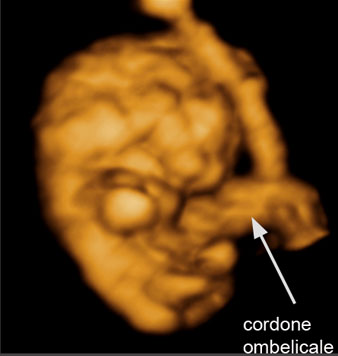

Fig. 3B

Embrione 10 mm: al 3D si iniziano a vedere gli arti e le parti del corpo.